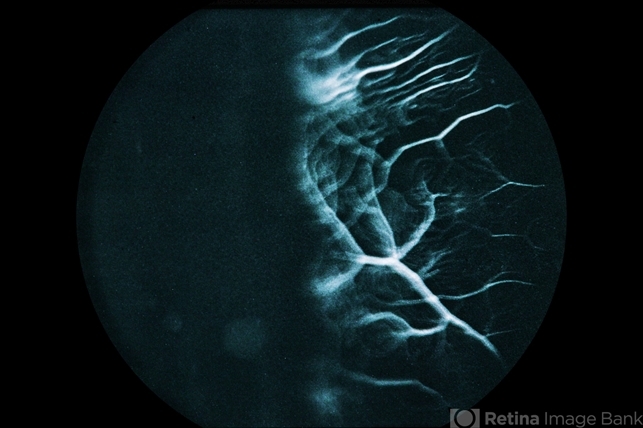

- Combined Retinal RPE Hamartoma

- combined hamartoma, retinal pigment epithelium (RPE) hamartoma

- 7-year-old black male with combined retinal / RPE hamartoma.